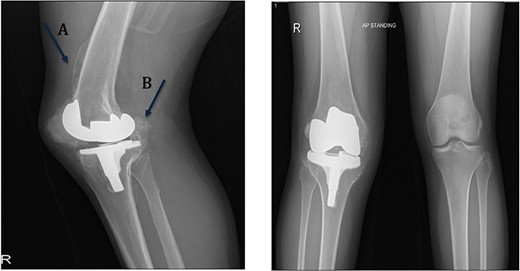

On the table, range of motion was 0–90°. Intraoperative image intensifier was used and demonstrated excellent position of the implant and the osteotomy site (Fig. 4).

The patient lost some of her range of motion (ROM) in the post-operative period even with extensive physiotherapy. On her 4-month follow up appointment; ROM was 10–80°, which she sustained afterward. Plain radiographs continued to show no new HO formation at 4 months (Fig. 5).

Intraoperative image intensifier demonstrated position of the implant, screw and the osteotomy site.

Knee X-rays at 4 months visit continued to show no new HO formation, and continuation of healing of the osteotomy.